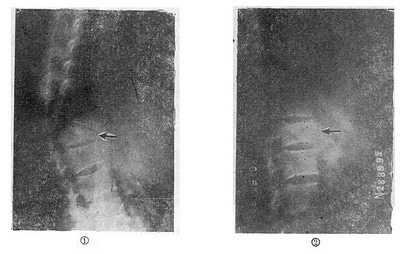

图73-12 垫枕背伸锻炼获良好结果

①骨折初时;②背伸锻炼3个月后